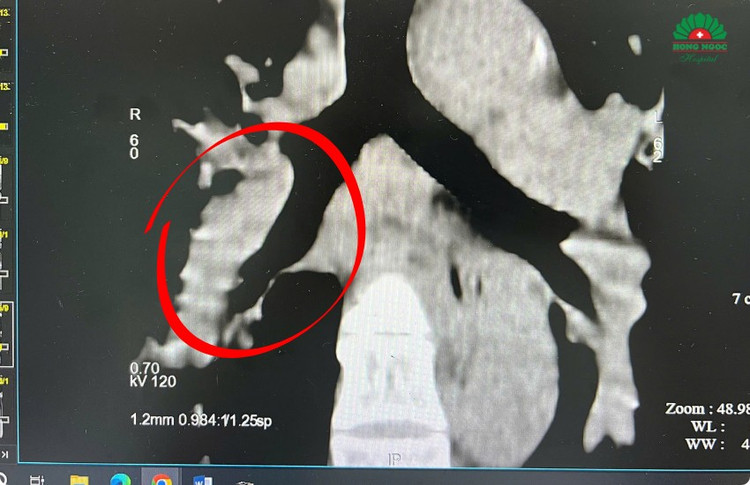

Ngay lập tức, chị P được chụp CT động mạch phổi để chẩn đoán xác định, kết quả cho thấy chị P. bị thuyên tắc động mạch phổi với mức nguy cơ trung bình cao - đúng như dự đoán ban đầu của bác sĩ.

doan-mach-bi-tac-18.png

Hình ảnh CT ghi nhận Thuyên tắc động mạch phổi - Ảnh BVCC